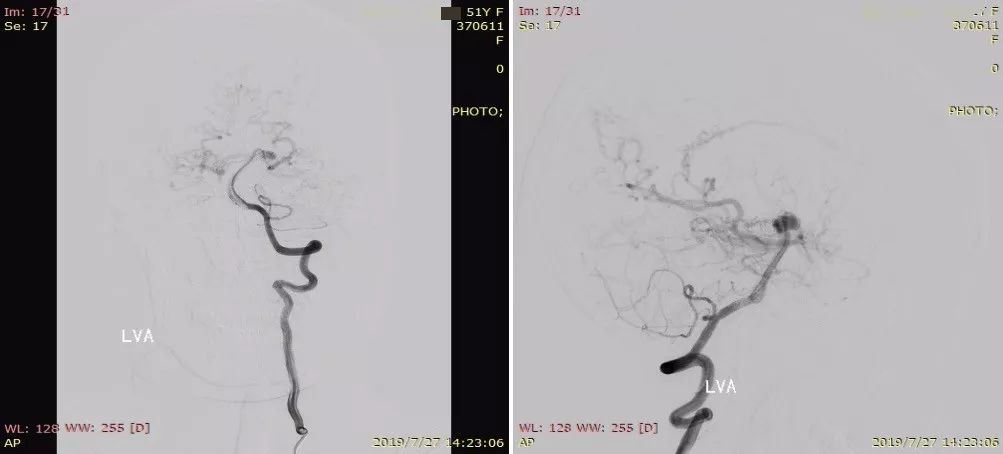

本次术前DSA(图3)

图3

颅内多发动脉瘤(左侧小脑上动脉)

蛛网膜下腔出血

烟雾病

左侧大脑后动脉狭窄